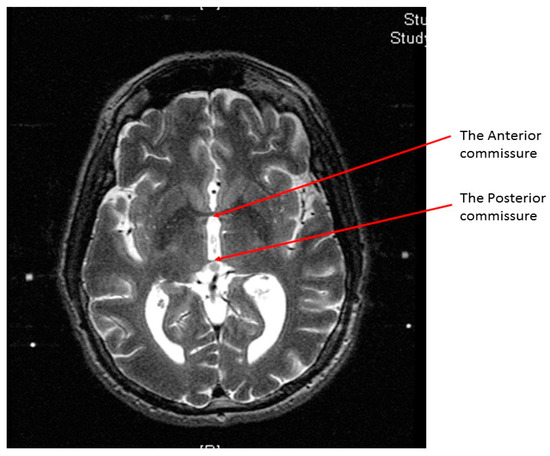

Figure 1.

An axial T2 weighted magnetic resonance image (MRI) at the level of the midbrain showing the two subthalamic nuclei (STN).

An axial T2 weighted magnetic resonance image showing the anterior commissure and the posterior commissure at the same cut.